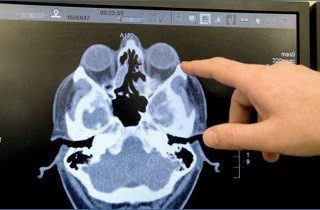

При выполнении компьютерной томографии на экране можно четко увидеть контуры, плотность, форму и структуру внутренней оболочки полостей пазух, слезных протоков, а также наличие минерализации. Это позволяет провести точную оценку размеров, состояния и структуры соустьев пазух носа. В процессе КТ-исследования быстро и безошибочно выявляются осложнения и последствия синуситов, такие как перегородочный (пресептальный) целлюлит, абсцессы краниального и орбитального отделов. Также при проведении КТ-исследования можно обнаружить врожденные или приобретенные нарушения вентиляции полости носа и ее придаточных пазух, такие как искривление перегородок, образование шпор, разрастание, изменения строения соустий и другие.

Компьютерная томография (КТ) предоставляет возможность оценить целостность костных тканей носа.